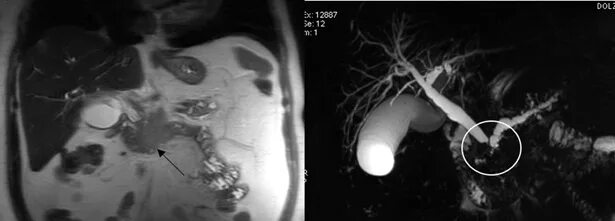

Ммрт